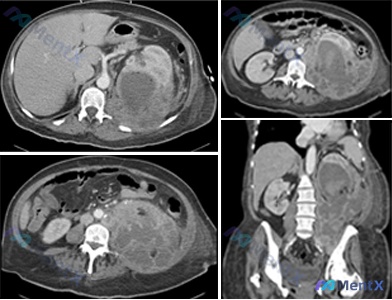

整理了一个肾脏占位病例,资料如下: 63岁男性,左胁饱胀感2个月,近期出现持续疼痛,有高血压病史,目前服用氯沙坦+氢氯噻嗪,既往史无特殊,有30包年吸烟史。 查体:体温37.7℃,左胁腹可触及10×10cm肿块,生命体征平稳。 检查结果: - 血红蛋白19.5g/dL,白细胞、血小板正常 - 尿检:...